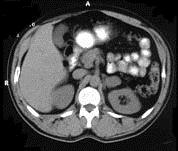

问题 女,34岁,无意中发现血压升高4 个月就诊,行CT检查,如图所示,下列说法正确的是 ( )

选项 A、考虑为左肾上腺嗜铬细胞瘤 B、考虑为左肾上腺转移瘤 C、增强扫描,该病灶周边明显强化,中心处强化不明显 D、考虑为左肾上腺腺瘤 E、CT示左侧肾上腺区可见一等密度块影,边界清楚

答案 ACE